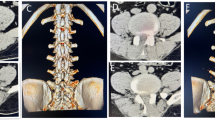

Kobayashi, S. et al. Imaging of cauda equina edema in lumbar canal stenosis by using gadolinium-enhanced MR imaging: experimental constriction injury. AJNR Am. J. Neuroradiol. 27, 346–353 (2006).